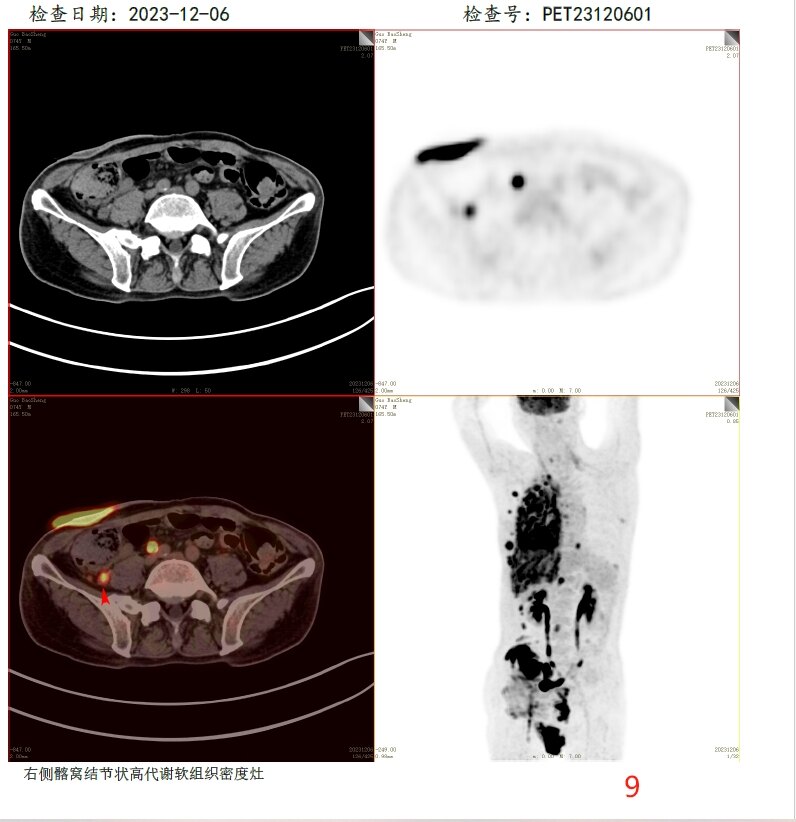

放疗前PET/CT(2023-12-06):

9